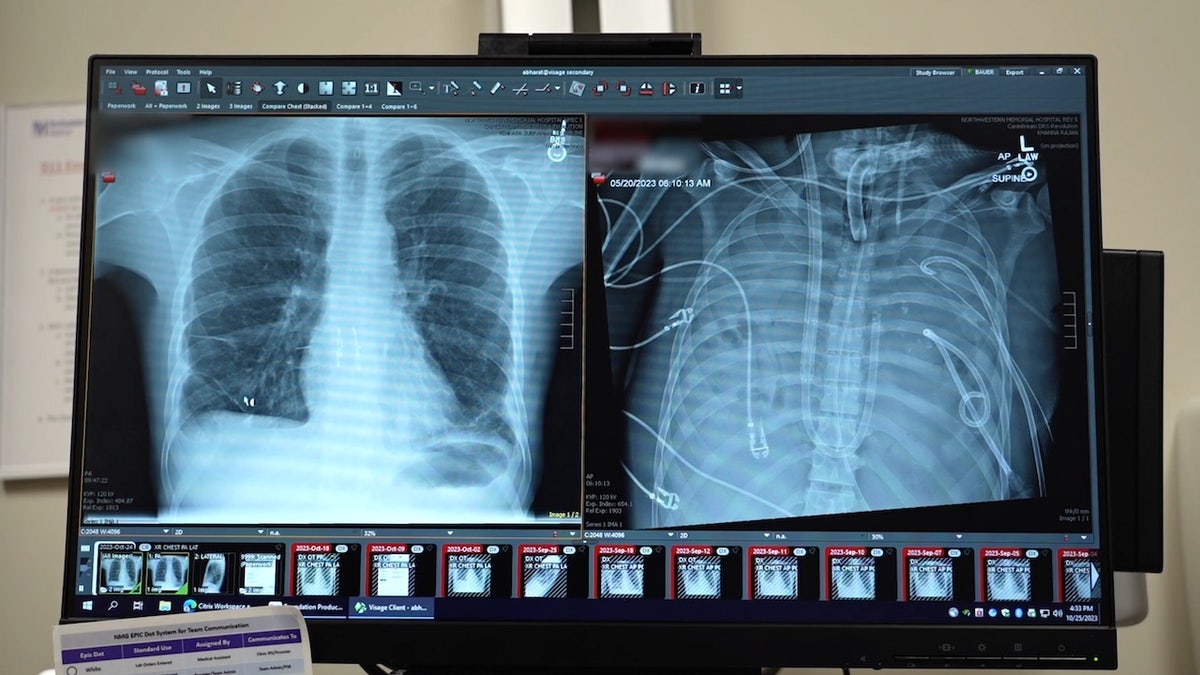

The patient’s new transplant is shown at left, and his old lungs are shown at right. “This technology allows us to ‘clean the slate’ by removing the infection, stabilizing the patient and bridging them to a successful transplant,” the lead surgeon said. (Northwestern Medicine)